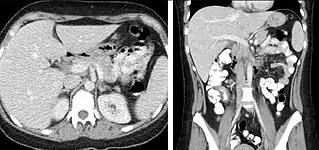

Detection and characterization of renal parenchymal masses is a frequent indication for CT. An initial noncontrast CT is important for detecting calcium or fat in a lesion, and to provide baseline attenuation of any renal masses. Following noncontrast scanning, intravenous contrast is injected and a corticomedullary phase is obtained at approximately 70 seconds (figure 7a, 7b). The corticomedullary phase is characterized by enhancement of the renal cortex as well as the renal vasculature. This phase is valuable in the evaluation of benign renal variants, lymphadenopathy and vasculature, however certain medullary renal masses may not be visible during this phase due to minimal enhancement of the medulla and collecting system. The parenchymal phase is obtained approximately 100–200 seconds after the injection of contrast material (figure 7c). Parenchymal phase imaging demonstrates continued enhancement of the cortex, enhancement of the medulla, and various levels of contrast material in the collecting system. The parenchymal phase is highly important for the detection and characterization of renal masses, parenchymal abnormalities, and the renal collecting system. This method of imaging does not evaluate for abnormalities of the collecting system.

Common renal masses can occasionally be differentiated from each other using this imaging technique. Renal cell carcinomas and oncocytomas typically demonstrate intense heterogeneous enhancement on the parenchymal phase images and cannot be reliably differentiated from each other but can be distinguished from other renal masses. Angiomyolipomas (AML’s) also demonstrate intense contrast enhancement but characteristically contain macroscopic fat which can be detected on the noncontrast images, and can help to differentiate AML’s from renal cell carcinomas and oncocytomas. Renal lymphoma on the other hand, will often have decreased enhancement when compared to the renal parenchyma on the parenchymal phase images.

FIGURE 7. Selected images from a renal mass specific protocol CT. Corticomedullary phase (axial 7a) demonstrates peripheral enhancement of the renal cortex with minimal opacification of the renal medulla. There is a large renal cell carcinoma in the left kidney (right in image) which can be differentiated from the normal renal parenchyma by the heterogeneous and differential enhancement. The renal artery and vein are opacified in this phase as well. The collecting system is not opacified (coronal reformat 7b). In the parenchymal phase, the renal cortex and the medulla are enhancing. The renal cell carcinoma in the left kidney is not as well defined when compared to the corticomedullary phase images, but is actually slightly more conspicuous. There is some contrast noted within the collecting system during this phase (7c).